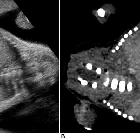

Antenatal ultrasound

Thus identification of a dividing membrane or two placentas excludes the diagnosis. Definitive sonographic features will depend on the type of fusion.

General features include:

- lack of a separating inter-twin membrane

- non-separable skin contours with an inability to separate the fetal bodies

- detection of other anomalies in a twin gestation

- solitary umbilical cord with more than 3 vessels present

- both fetal heads persistently at the same level

- backward flexion of the cervical spine (due to the fact that most conjoined twins are fused ventrally and face each other

- bibreech or less commonly, bicephalic presentation

- constant relative fetal positions